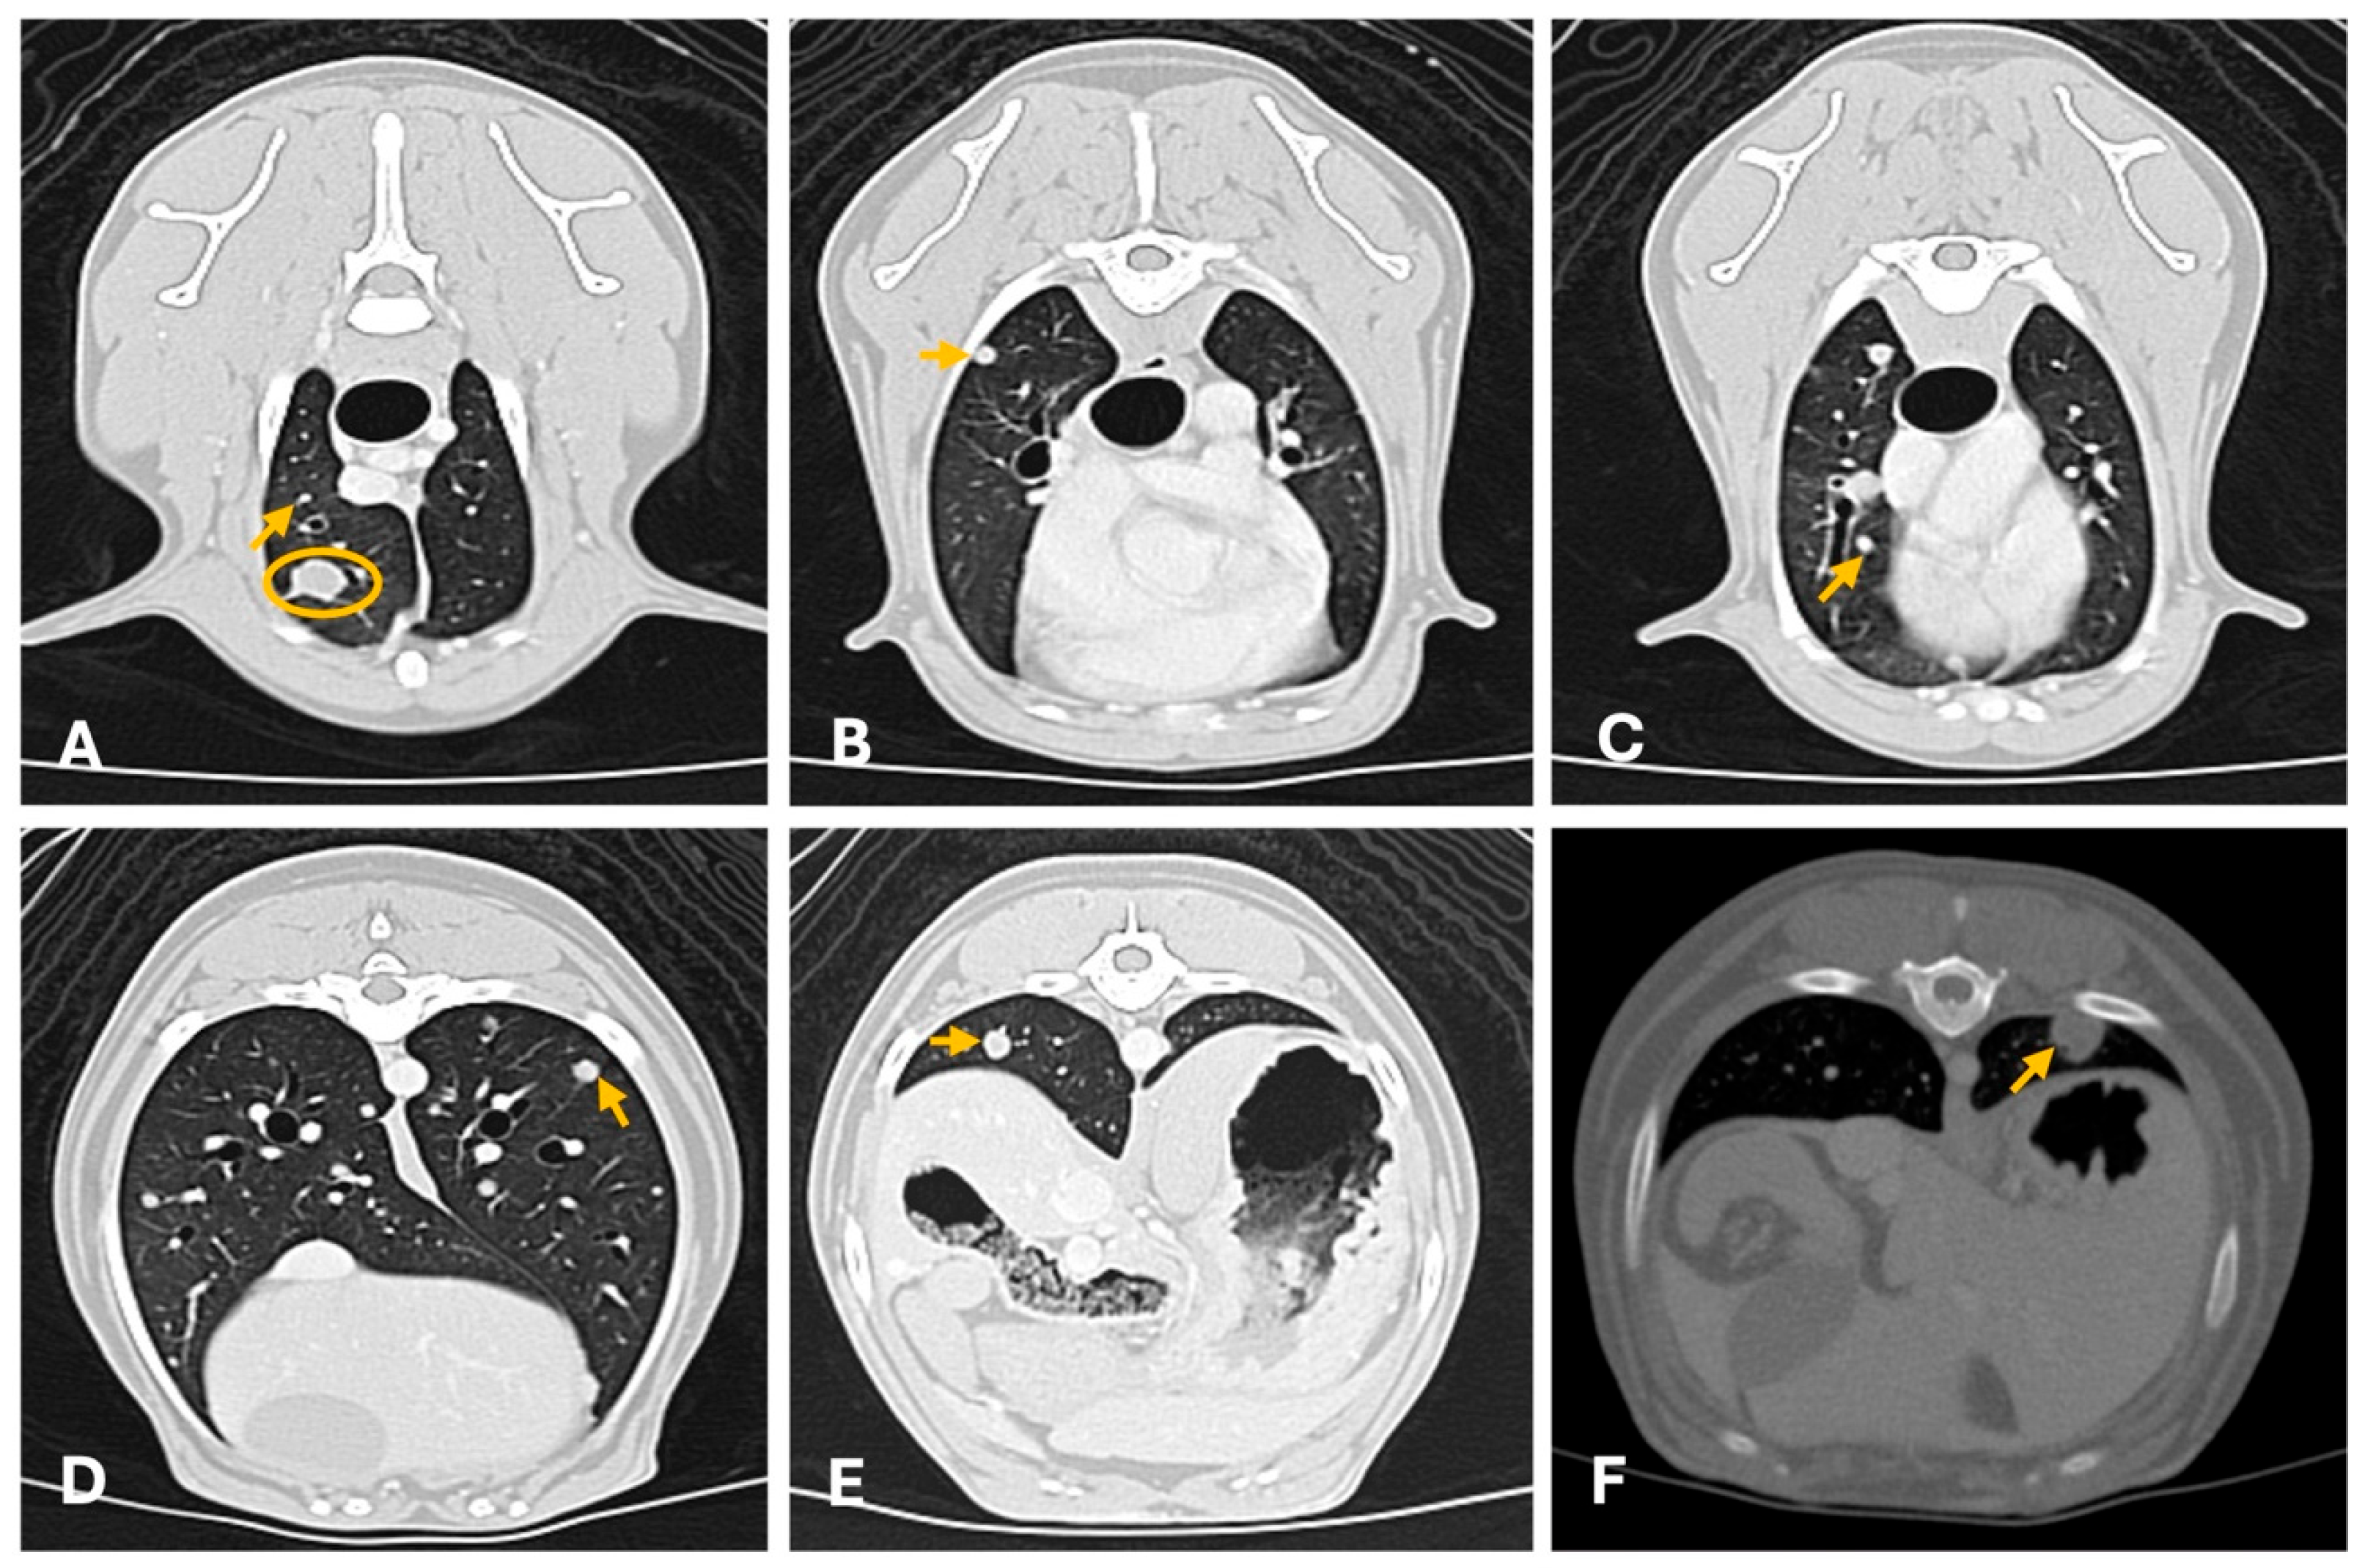

4.2. Computed Tomography

- Lamb, C.R.; Whitlock, J.; Foster-Yeow, A.T.L. Prevalence of Pulmonary Nodules in Dogs with Malignant Neoplasia as Determined by CT. Vet. Radiol. Ultrasound 2019, 60, 300–305. [Google Scholar] [CrossRef]

- Armbrust, L.J.; Biller, D.S.; Bamford, A.; Chun, R.; Garrett, L.D.; Sanderson, M.W. Comparison of Three-View Thoracic Radiography and Computed Tomography for Detection of Pulmonary Nodules in Dogs with Neoplasia. J. Am. Vet. Med. Assoc. 2012, 240, 1088–1094. [Google Scholar] [CrossRef]

- Klaengkaew, A.; Sutthigran, S.; Thammasiri, N.; Yuwatanakorn, K.; Thanaboonnipat, C.; Ponglowhapan, S.; Choisunirachon, N. The Evaluation of Non-Anesthetic Computed Tomography for Detection of Pulmonary Parenchyma in Feline Mammary Gland Carcinoma: A Preliminary Study. BMC Vet. Res. 2021, 17, 237. [Google Scholar] [CrossRef] [PubMed]